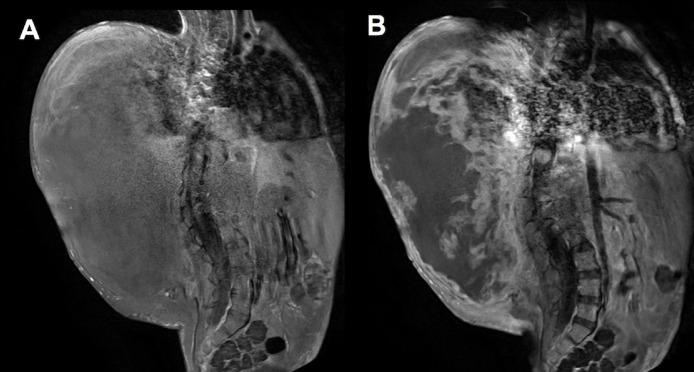

Malignant peripheral nerve sheath tumors (MPNSTs) are rare but aggressive neoplasms associated with neurofibromatosis type 1. Specifically, children with deep plexiform neurofibromas are 18 times more likely to develop MPNSTs compared to the general population. However, there is currently no standard surveillance imaging protocol for children diagnosed with deep plexiform neurofibromatosis. We present a case of a boy with neurofibromatosis type 1 and scoliosis, who later developed MPNST. This case highlights the need for more frequent surveillance imaging and the challenges of diagnosing MPNST in a patient with scoliosis. In order to facilitate early detection of malignant transformation, we suggest annual surveillance MR imaging for patients known to have deep plexiform neurofibromatosis.

摘要

恶性外周神经鞘瘤(MPNSTs)虽罕见但具有侵袭性,与1型神经纤维瘤病相关。具体而言,患有深部丛状神经纤维瘤的儿童发生MPNSTs的可能性是普通人群的18倍。然而,目前对于诊断为深部丛状神经纤维瘤病的儿童尚无标准的监测成像方案。我们报告一例患有1型神经纤维瘤病和脊柱侧弯的男孩,其后来发展为MPNST。该病例凸显了更频繁进行监测成像的必要性以及在脊柱侧弯患者中诊断MPNST的挑战。为便于早期发现恶性转化,我们建议对已知患有深部丛状神经纤维瘤病的患者每年进行监测性磁共振成像检查。